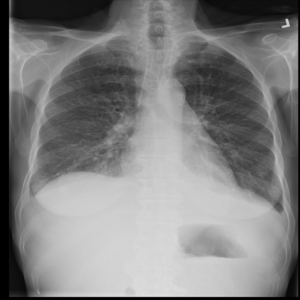

Anomaly detection is the problem of recognizing abnormal inputs based on the seen examples of normal data. Despite recent advances of deep learning in recognizing image anomalies, these methods still prove incapable of handling complex medical images, such as barely visible abnormalities in chest X-rays and metastases in lymph nodes. To address this problem, we introduce a new powerful method of image anomaly detection. It relies on the classical autoencoder approach with a re-designed training pipeline to handle high-resolution, complex images and a robust way of computing an image abnormality score. We revisit the very problem statement of fully unsupervised anomaly detection, where no abnormal examples at all are provided during the model setup. We propose to relax this unrealistic assumption by using a very small number of anomalies of confined variability merely to initiate the search of hyperparameters of the model. We evaluate our solution on natural image datasets with a known benchmark, as well as on two medical datasets containing radiology and digital pathology images. The proposed approach suggests a new strong baseline for image anomaly detection and outperforms state-of-the-art approaches in complex medical image analysis tasks.

翻译:异常检测是根据正常数据实例识别异常输入的问题。尽管在识别图像异常方面最近取得了深层次学习的进展,但这些方法仍然证明无法处理复杂的医学图像,如胸部X光几乎看不到异常和淋巴节点转移等。为了解决这一问题,我们引入了一种新的强有力的图像异常检测方法。它依靠古典的自动解剖器方法,经过重新设计的培训管道来处理高分辨率、复杂图像和图像异常分数。我们重新审视了完全不受监督的异常点检测的非常问题说明,在模型设置期间,根本没有提供异常的例子。我们提议放松这一不现实的假设,仅使用少量有限的异常点来开始搜索模型的超参数。我们评估我们使用已知基准的天然图像数据集以及包含放射学和数字病理图像的两个医疗数据集的解决方案。拟议方法为在复杂的医学图像分析任务中,为图像异常点检测和超常规状态方法提供了新的强基线。